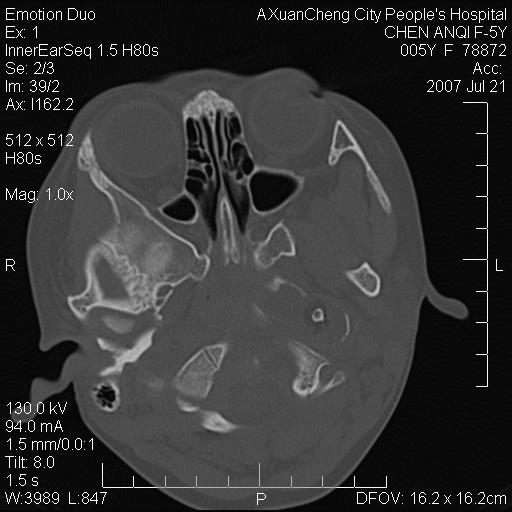

标题: PED0273:5岁,左耳流脓痛疼一周,颅底骨质破坏 [打印本页]

标题: PED0273:5岁,左耳流脓痛疼一周,颅底骨质破坏

患儿5岁,左耳流脓痛疼一周,左外耳道肉芽组织填塞 软组织窗显示病灶内结节状低密度影为气体密度

1.左耳中耳炎. 2.考虑伴颅内感染.

颅底骨质破坏,建议增强扫描

左侧中耳炎并胆脂瘤,左颞骨岩部骨质破坏并颅内感染积气。